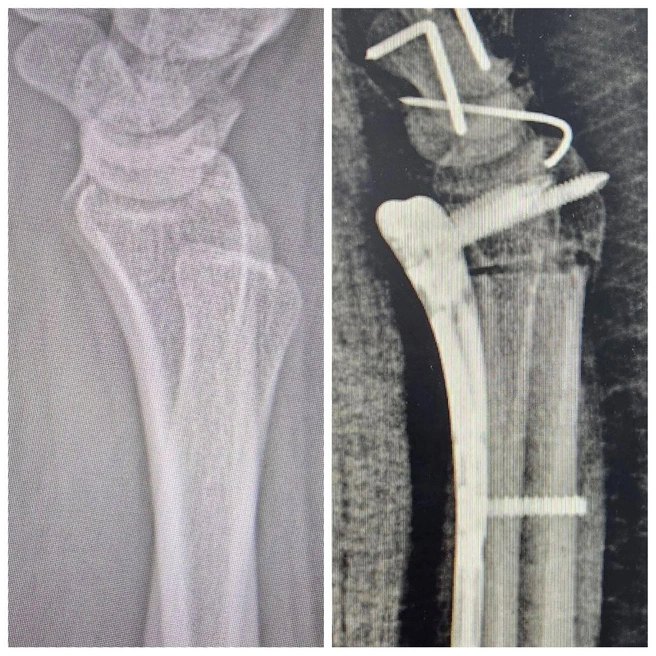

Пересадили уничтоженную кость

У 24-летней тюменки около года болело запястье. Врачи обследовали ее и обнаружили очень редкую патологию — болезнь Кинбека. Из-за нее в руке нарушается кровоснабжение и отмирает полулунная кость. Хирургам предстояло пересадить пациентке кость и вернуть руке подвижность.

Сначала специалисты Центра реконструктивной микрохирургии кисти провели остеотомию, чтобы уменьшить давление на поврежденную кость.

Остеотомия — это хирургическая операция по искусственному разрезанию кости для коррекции ее формы, положения или длины.

После этого врачи взяли у девушки фрагмент подвздошной кости, сохранив его кровеносные сосуды. Их сразу же подшили к сосудам запястья, чтобы питать полулунную кость. Операция прошла успешно. После шести недель покоя пациентка приступила к реабилитации.